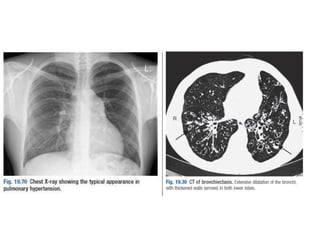

Figure 11.32 Left atrial dilatation.

This is a penetrated PA chest X-ray in a patient with mitral stenosis.

The dilated left atrium causes a bulge on the left heart border below

the pulmonary artery which is also dilated, widening of the carina

and the double density sign at the right heart border.